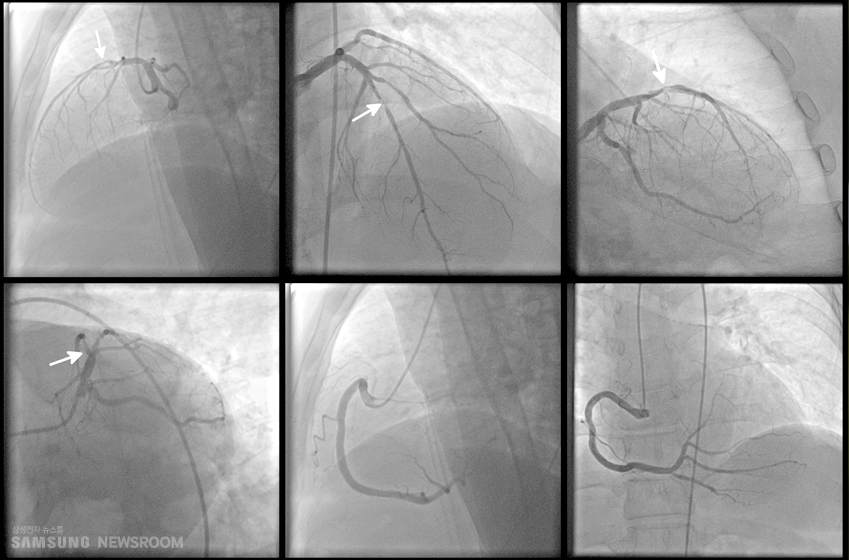

환자의 상태에 따라 약물치료, 시술 및 수술 등의 치료를 할 수 있어요. 협심증이 심각한 경우 혹은 약물 치료에도 반응하지 않을 때는 관상 동맥 우회술 혹은 관상 동맥 성형술과 같은 다른 선택이 권장될 수 있어요. 환자 개개인에게 제일 적당한 치료 계획을 결정하기 위해서는 꼭 의사와 상담하는 것이 중요해요.

약물 치료의 경우에는 협심증의 원인인 동맥 경화증을 예방하고 진행을 막는 치료법이며, 협심증에 의해 혈관이 80% 이상 좁아져 있어서 심장 시술이나 수술이 필요하게 될 때 스텐트 시술, 풍선 확장술 및 관상 동맥 우회로술 등의 수술을 하는 것인데요.

협심증 초기증상이 있다가 없다가를 반복하며 병원에 방문하려다가 또 증상이 없어서 방치하다 보면 질환이 더욱더 심각해질 수 있어요. 특히나 관상동맥 혈관이 80% 이상 좁아지기 전까지는 심장초음파 검사에서는 정상이라고 진단받는 경우가 많기 때문에 보다 정밀한 검진을 위한 관상 동맥 질환에 특화된 검진을 받는 것이 필요해요.